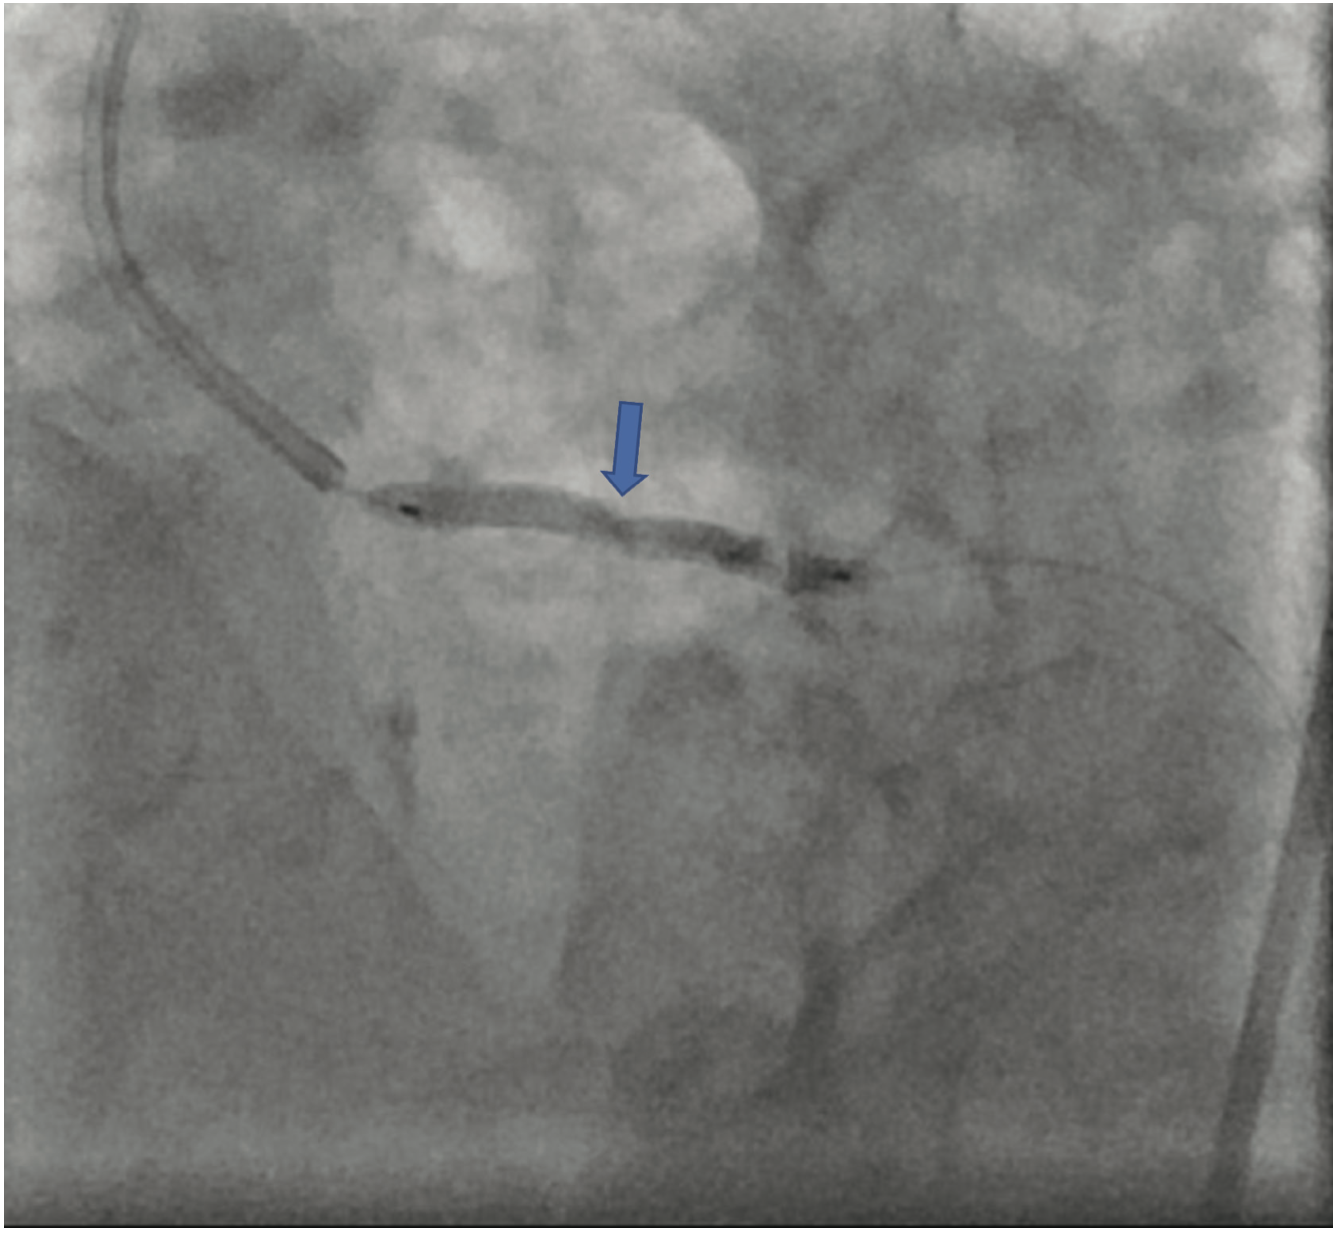

The patient’s electrocardiogram showed sinus rhythm with left bundle branch block and echocardiography demonstrated a normal left ventricular ejection fraction with a transvalvular aortic mean gradient of 10 mmHg. On further evaluation, his nuclear stress test showed severe anterior ischemia. A review of his previous angiograms demonstrated an underexpanded stent in the distal LM that was potentially constrained by a circumferential calcific lesion (Figure 1). Intravascular ultrasound (IVUS) and atherectomy were not utilized during the index procedure. The patient underwent cardiac catheterization via the right femoral approach, which demonstrated severe in-stent restenosis (ISR) of the distal LM due to an underexpanded/undersized stent (Figure 2), confirmed on assessment of the non-contrast chest imaging and IVUS, with a minimum stent area (MSA) of 4 mm2 (Figure 3). Given the patient was not a surgical candidate, further percutaneous management was elected as the best management strategy since the patient had refractory angina despite medical therapy. Mechanical support with large-bore access was not feasible, given the vascular disease in his lower extremities had worsened, and with severe carotid disease, the patient was not a candidate for axillary large-bore devices. He was pre-treated with aspirin and clopidogrel before the PCI.